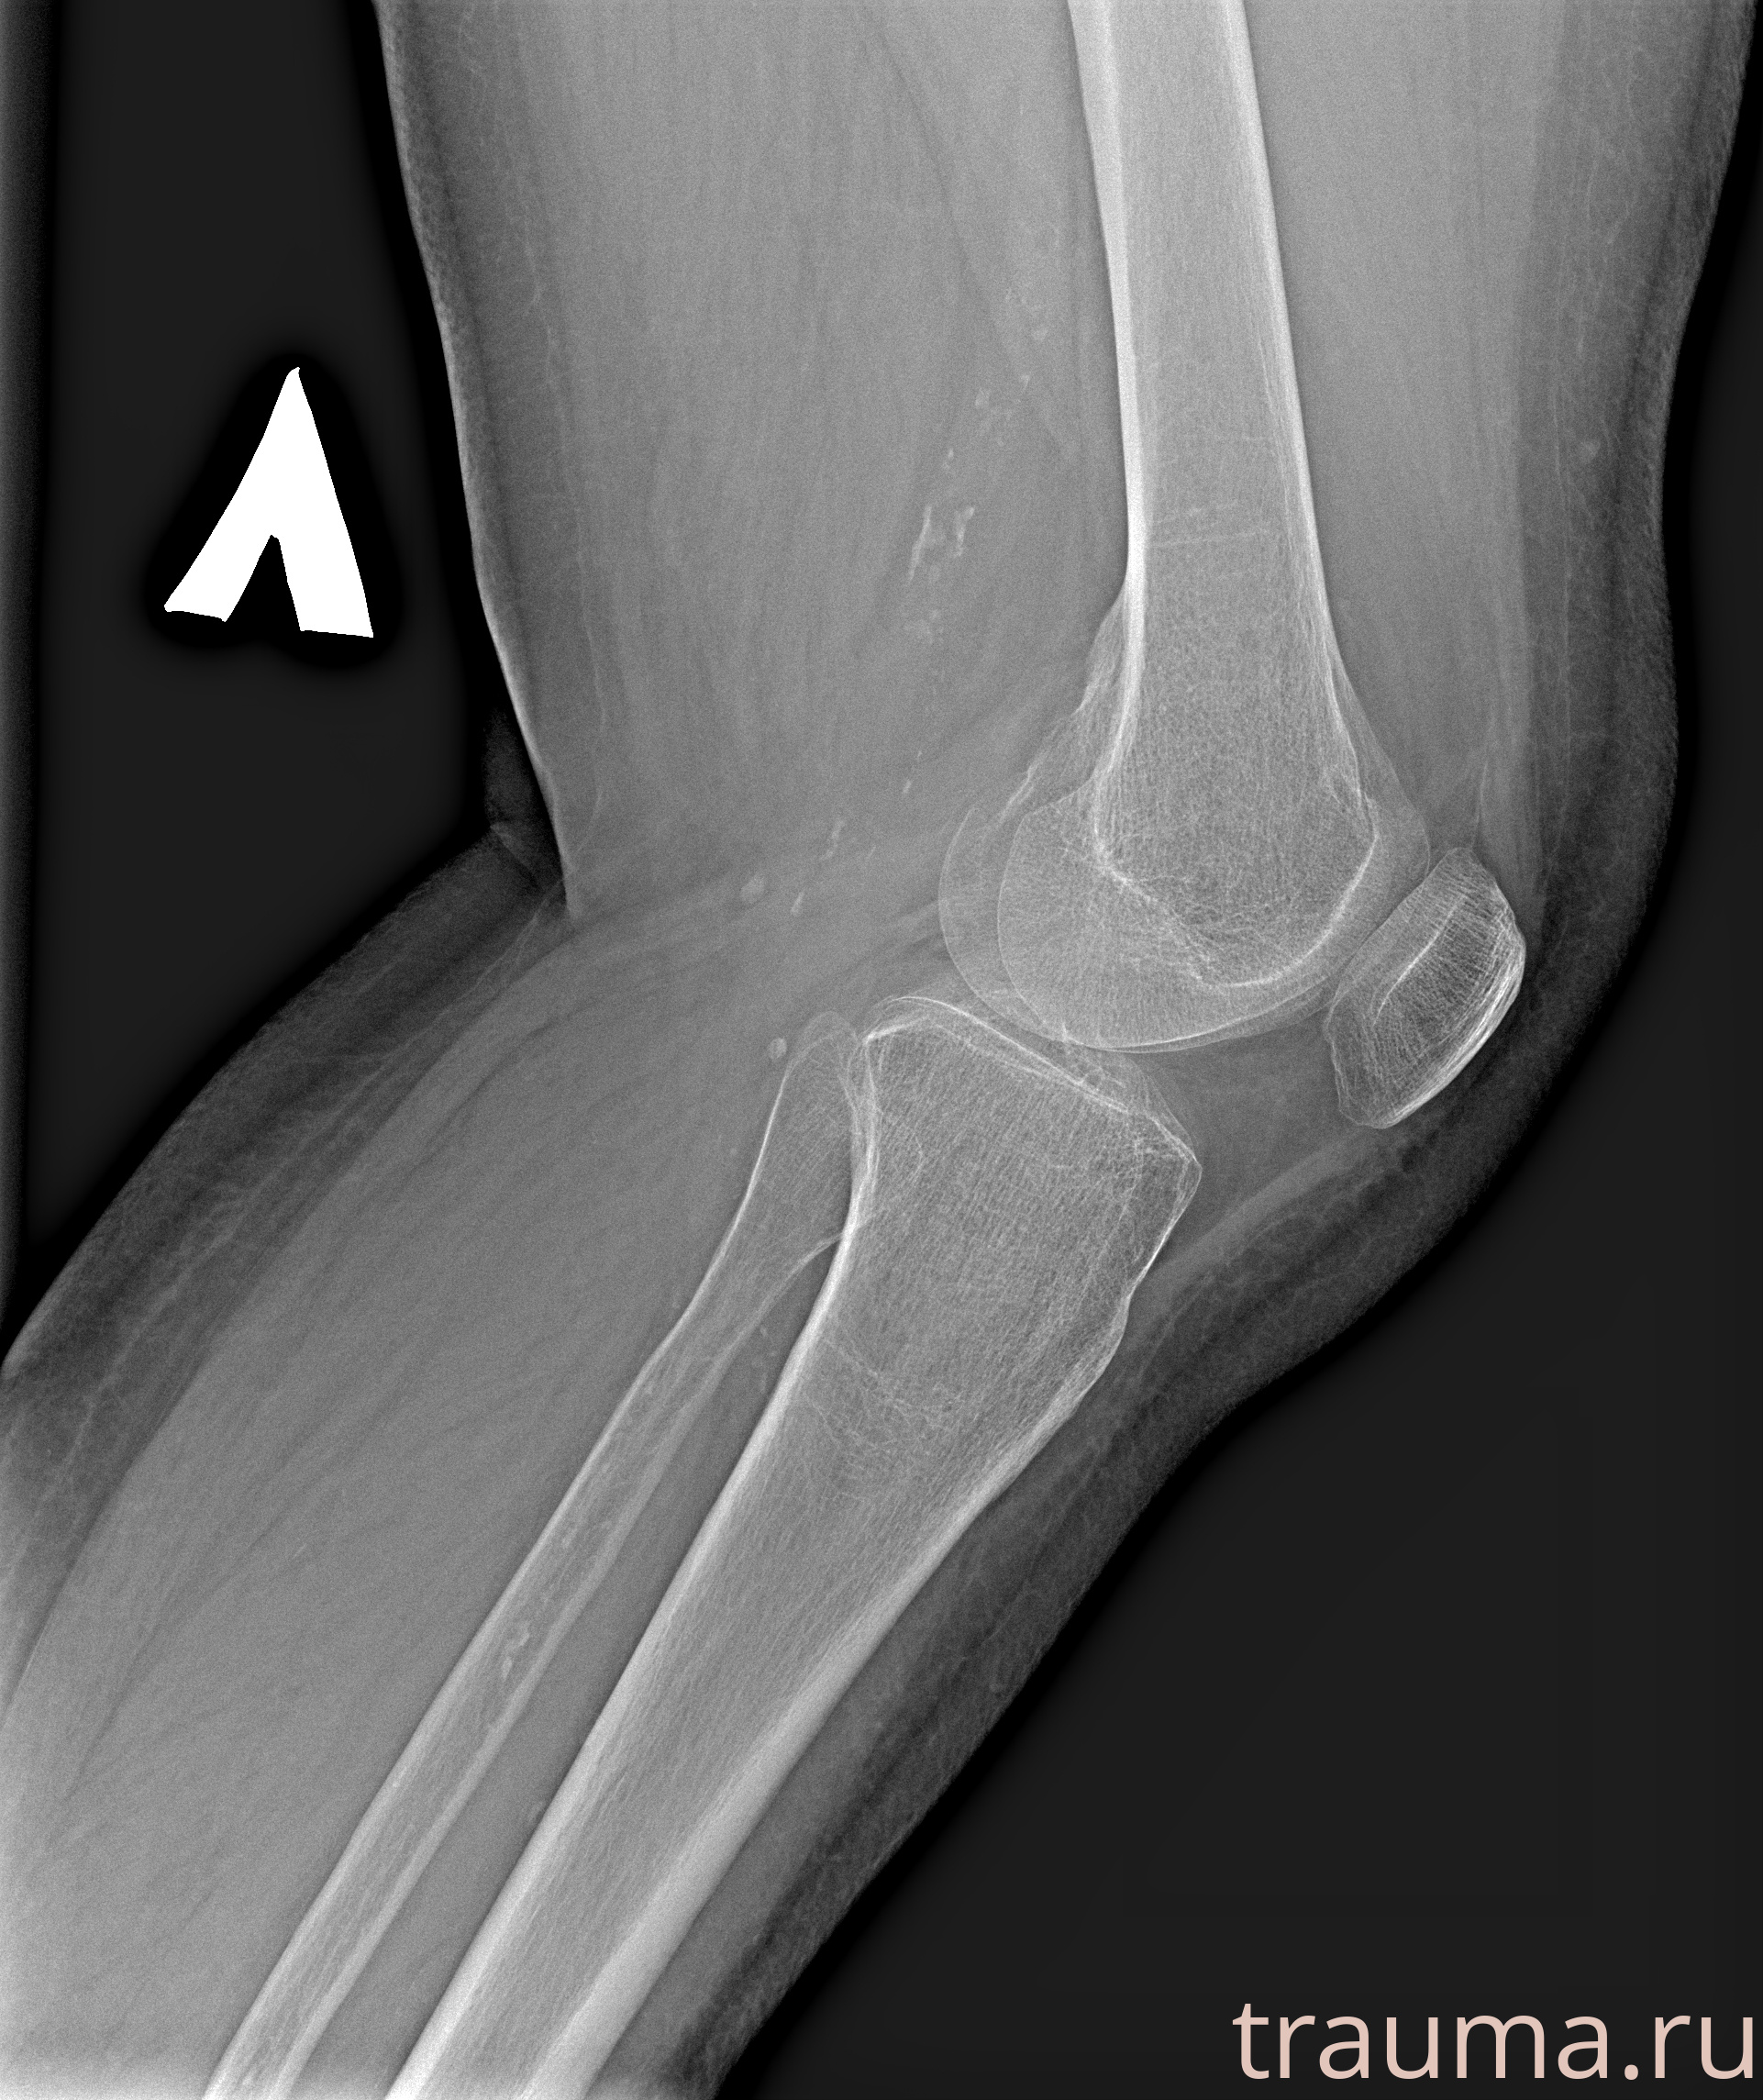

Рентгенограммы

Рентген на дому: по вашему адресу приезжает врач-рентгенолог, травматолог-ортопед с мобильным рентгеновским аппаратом, проводит диагностику травмы или заболевания, делает необходимые рентгенограммы, дает рекомендации по дальнейшему лечению. Получить качественные снимки в домашних условиях возможно благодаря уникальной методике, разработанной МосРентген Центром для института  Склифосовского